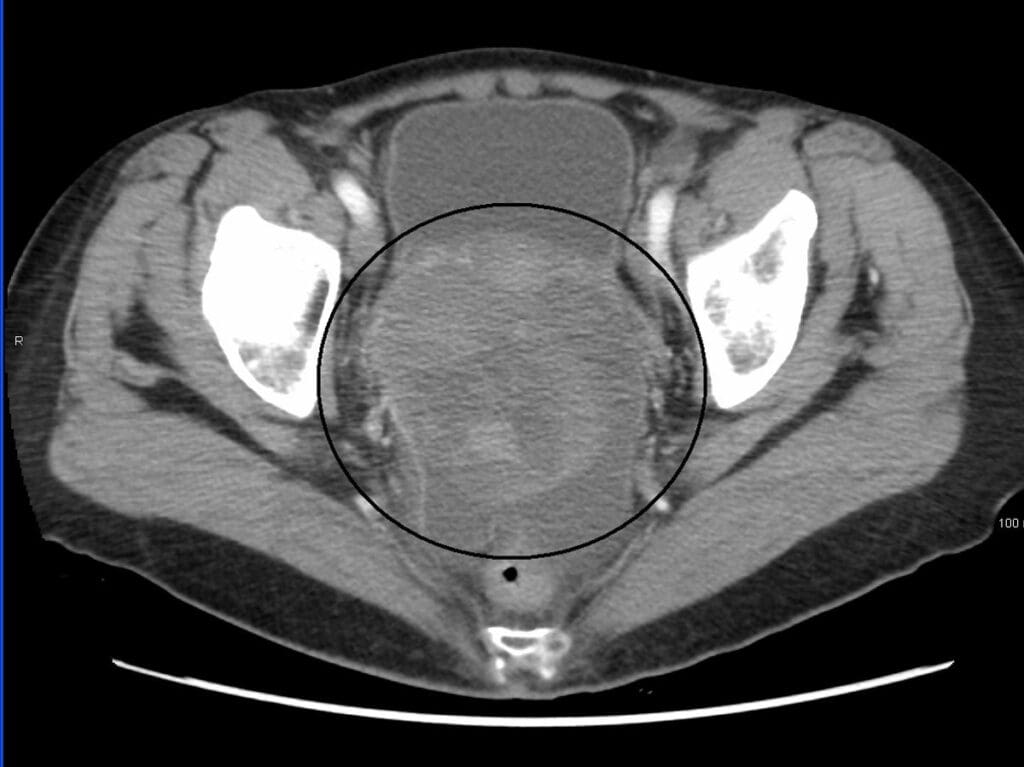

CT scans use x-rays to create detailed images of the bladder. They help find tumors. CT scans are great because they show tumors’ size, shape, and where they are in the bladder.

How CT Technology Visualizes Bladder Abnormalities

CT technology takes x-rays of the bladder from different angles. Then, it makes cross-sectional views. This lets doctors see the bladder in detail.

“A CT urogram can find urinary tract problems or enlarged lymph nodes with cancer,” doctors say. This helps them see how big tumors are and plan treatment.

We use CT scans to see the bladder because they show everything. The detailed images help doctors find problems that other tests miss.

The Role of Contrast in Tumor Detection

Contrast dye makes bladder problems stand out more in CT scans. Contrast agents show the differences between tissues, making tumors easier to see. Doctors say, “Contrast dye makes tumors more visible by highlighting them against other tissues.”

With contrast dye, CT scans can better spot tumors and understand their features. This info is key for choosing the right treatment for bladder tumors.